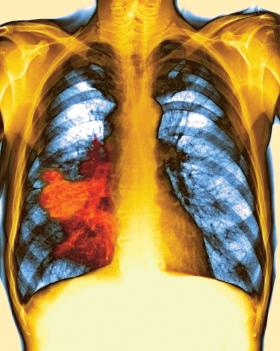

Na pokolorowanym zdjęciu rentgenowskim czerwony obszar to rozrośnięty rak prawego płuca.Getty Images Na pokolorowanym zdjęciu rentgenowskim czerwony obszar to rozrośnięty rak prawego płuca.